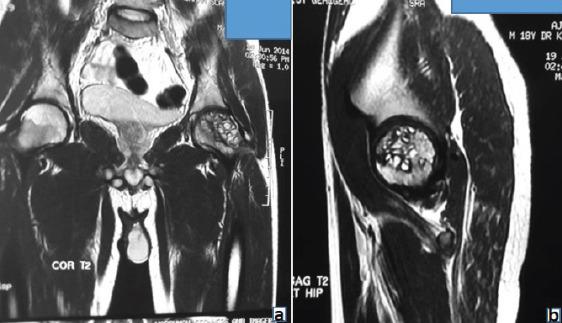

An 18-year-old male patient presented with the left groin pain and terminal restriction of hip movement for 1 year duration. The patient underwent open biopsy and histopathological examination of tissue specimen revealed hydatid cyst. The patient was started on albendazole and after 3 months, surgical curettage and removal of cysts were performed with application of bone cement. At 8 years follow-up, the patient is asymptomatic and doing well.

一名18岁男性患者,左侧腹股沟疼痛并伴有髋关节活动终末受限1年。患者接受了开放活检,组织标本的组织病理学检查显示为包虫囊肿。患者开始服用阿苯达唑,3个月后进行了手术刮除并应用骨水泥去除囊肿。随访8年,患者无症状,恢复良好。